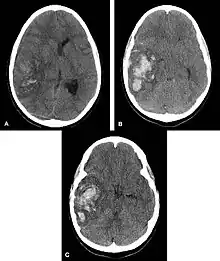

![]() | |

| Multiple intraparenchymal hemorrhage | |

Computed tomography (CT scan): A CT scan may be normal if it is done soon after the onset of symptoms. A CT scan is the best test to look for bleeding in or around your brain. In some hospitals, a perfusion CT scan may be done to see where the blood is flowing and not flowing in your brain.